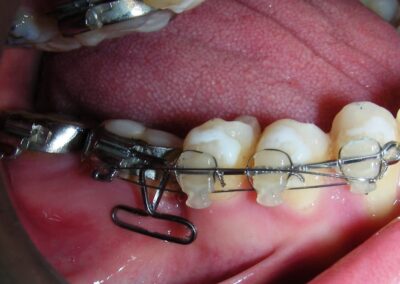

Was installed a Hyrax-type 10mm palatal expander of the Brazilian trademark Morelli® , modified by the author to be adapted to receive TADs microscrews, in order to initiate maxillary disjunction with MARPE (Mini-implant Assisted Rapid Palatal Expansion), TADS was installed with skeletal anchorage placed bilaterally having as references the roots of the maxillary canines and first premolars. Prior to insertion, local infiltrative anesthesia was administered using 2% lidocaine hydrochloride with 1:100,000 epinephrine. A total dose of approximately 0,8 mL per side (cortical infiltration technique). The TADs were inserted under aseptic conditions using a manual driver. Microscrew Evolution 1,6 Ø x 10 mm from the Argentine brand Odontit® . The Hyrax expander was then fitted and activated after 48 hrs .

Protocol of one activation per day was followed for a period of three weeks where the first clinical and radiographic evaluation was performed, showing clear signs of skeletal expansion, including the presence of a midline diastema. One more week of activations was added with a total of 28. The patient reported moderate headache during the first week of activation.

Having successfully achieved the expansion, we proceed to the intrusion of the posterior superior sectors, modifying the Hyrax by adding anchoring hooks at the buccal level of the first premolars. Using the Hyrax as anchorage, we sought a parallel intrusion. This could be replaced by a palatal bar. TADs were installed bilaterally at the mesial level of the first molars, inserting them as parallel as possible to the roots.